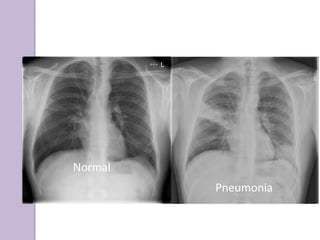

Normal

Pneumonia

Infiltrate Patterns

Pattern Possible Diagnosis

Lobar S. pneumo, Kleb, H. flu, GN

Patchy Atypicals, viral, Legionella

Interstitial Viral, PCP, Legionella

Cavitary Anaerobes, Kleb, TB, S. aureus,

fungi

Large effusion Staph, anaerobes, Kleb.